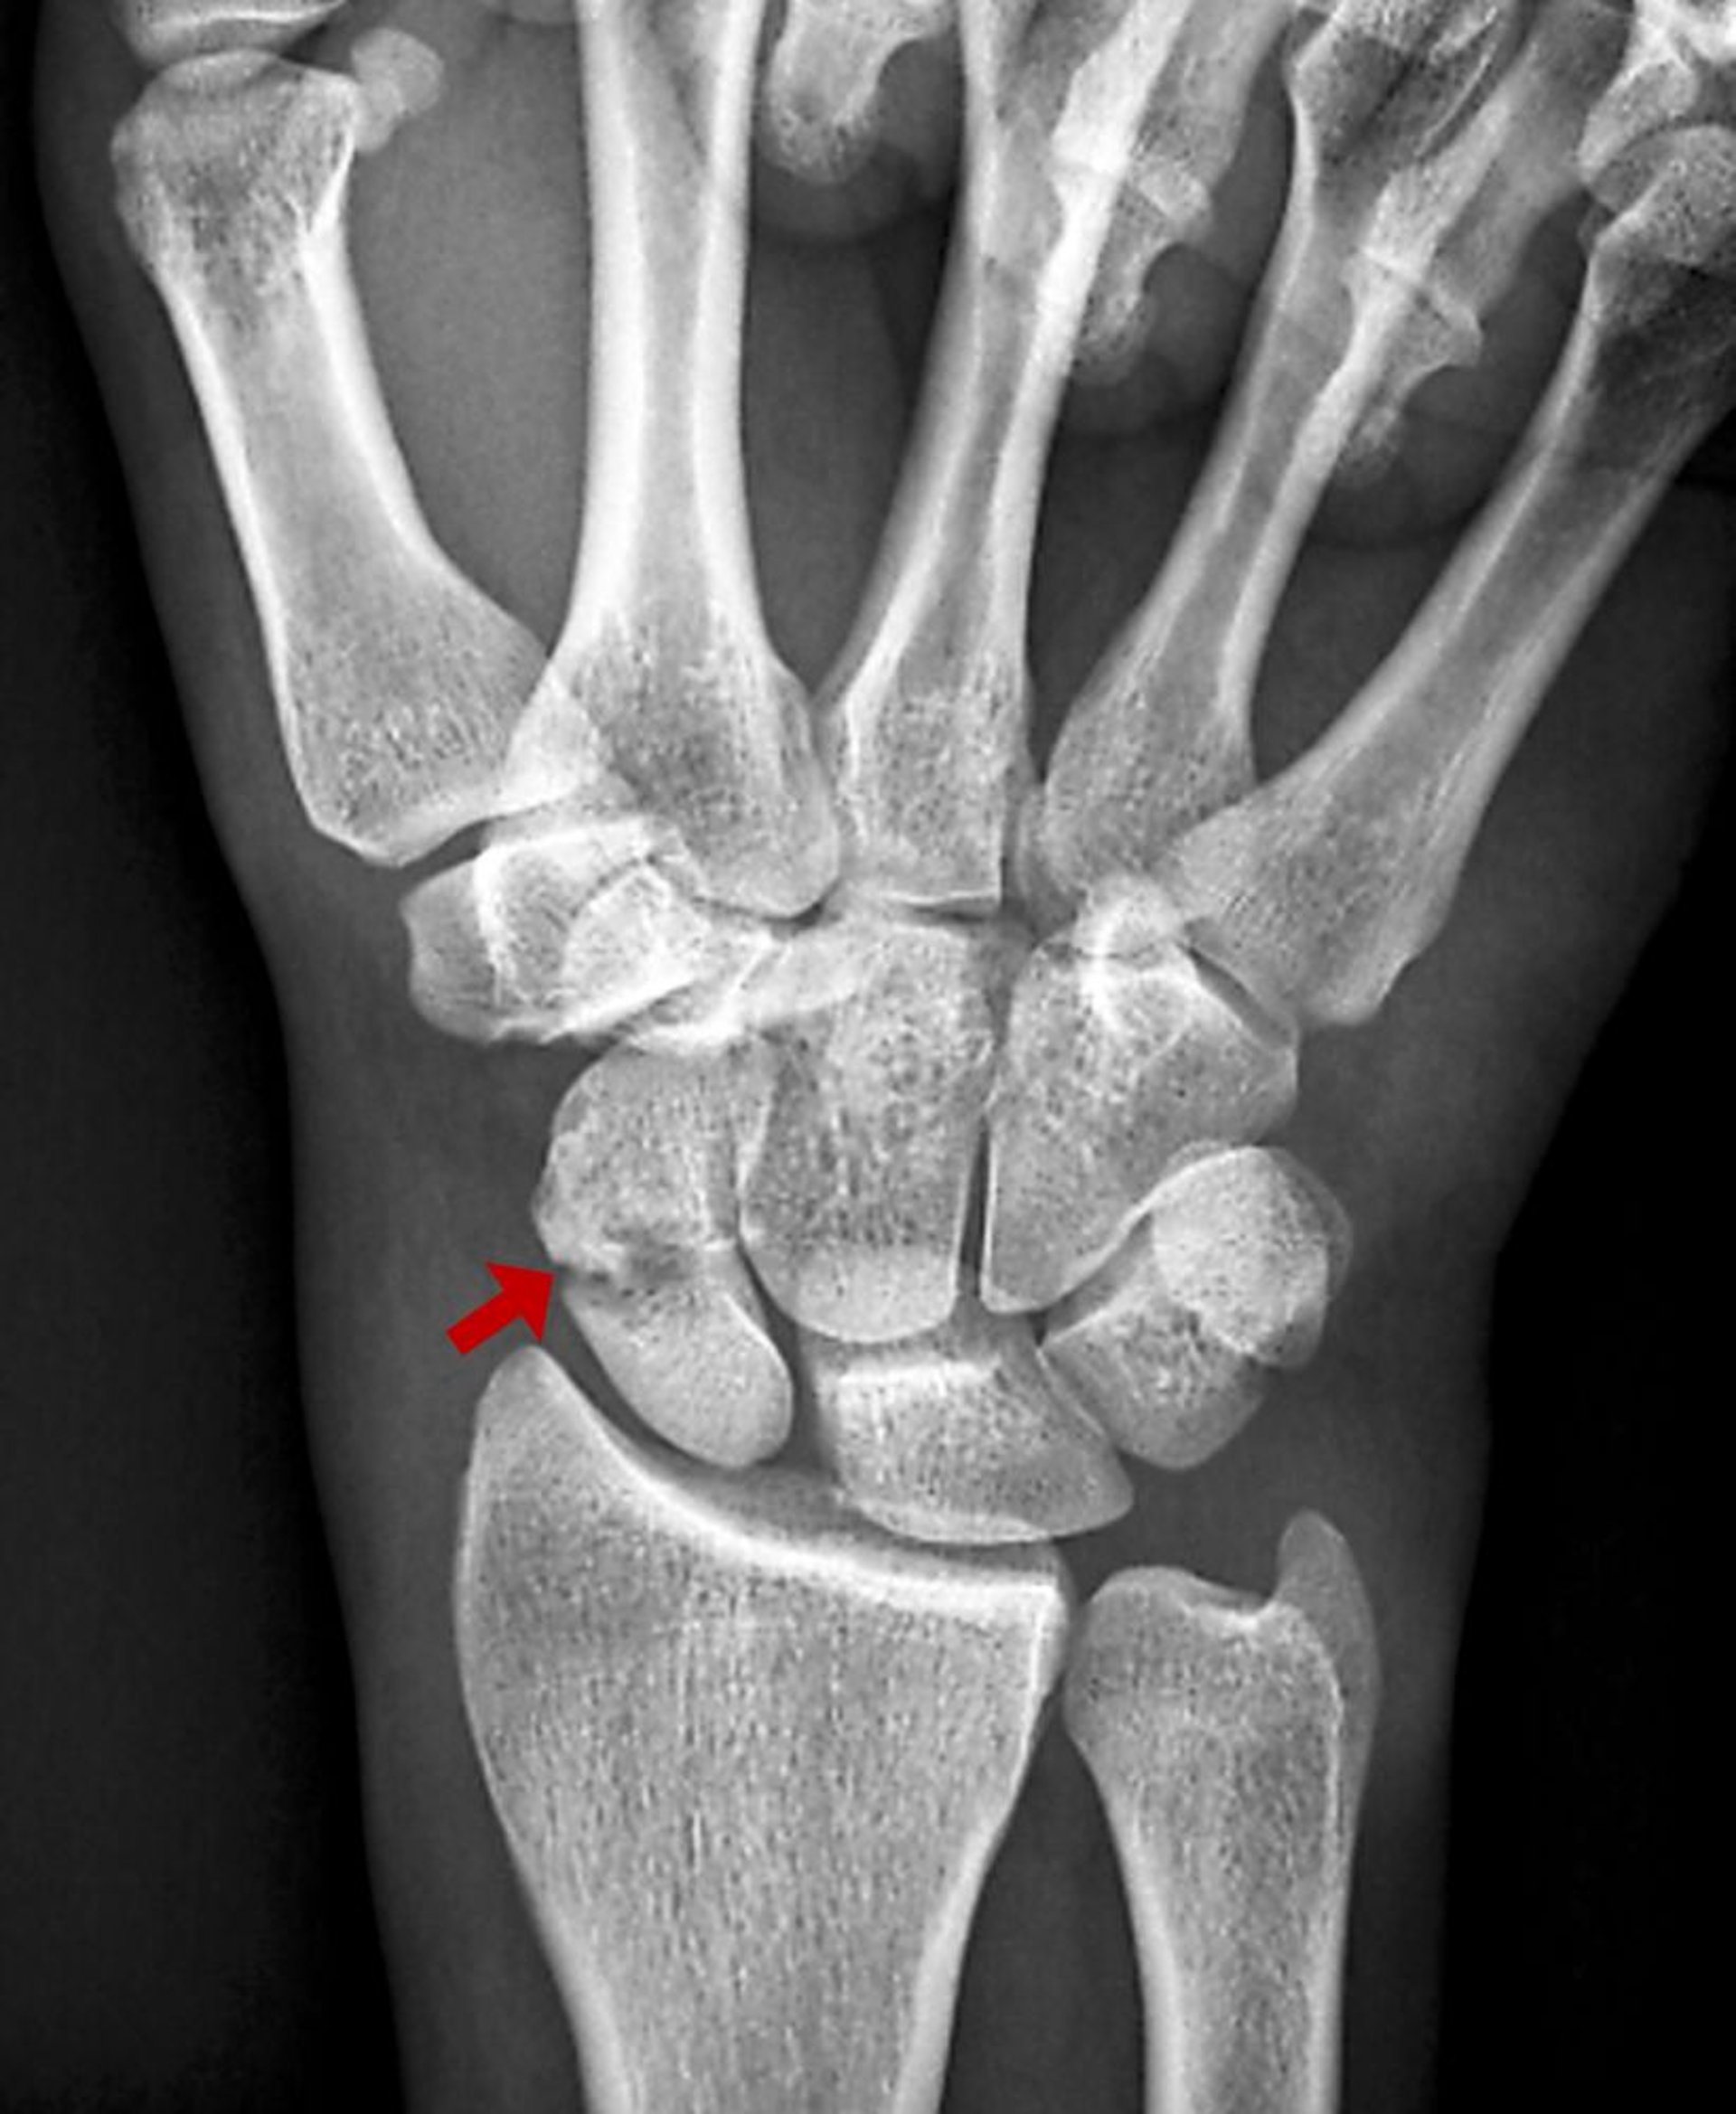

Fraturas do escafoide geralmente resultam de hiperextensão do punho. Podem não ser visíveis nas radiografias iniciais. As complicações podem ser graves.

O escafoide é o osso do carpo mais comumente lesado. Fraturas do escafoide usualmente resultam da hiperextensão do punho, geralmente durante uma queda sobre a mão estendida. Podem interromper o suprimento de sangue à porção proximal do escafoide. A osteonecrose é uma complicação comum, mesmo quando o cuidado inicial for ideal, e pode causar deficiência e artrite degenerativa no punho.

Inicialmente, são feitas radiografias simples (incidências ântero-posterior, lateral e oblíqua), mas estas frequentemente aparecem normais. Apenas cerca de 70% das fraturas do escafoide são vistas nas radiografias iniciais (1).